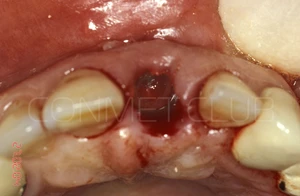

Вид на лунку удаленного зуба. Щипцы при удалении не использовались, только кюретажная ложка СМ 2/4 и прямой элеватор.

Сразу после экстракции зуба 21 производится установка имплантата КОНМЕТ с полированной трансгингивальной частью высотой более 3 мм. Интерфейс имплантата - просто конус Морзе и ни каких антиротационных шестигранников!